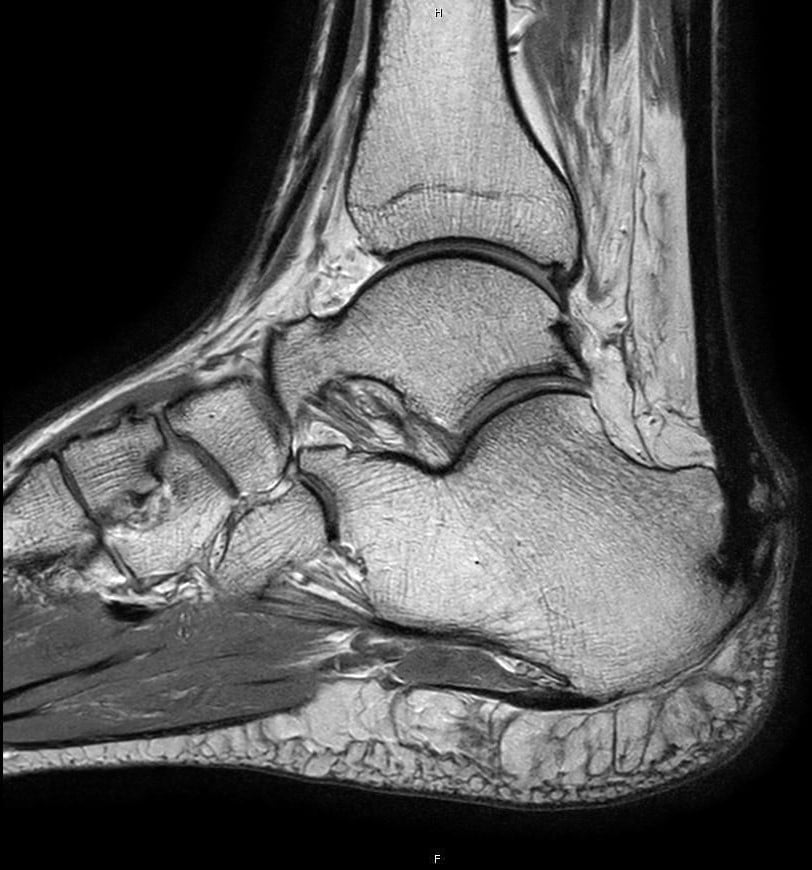

Inflammation of the Achilles’ tendon where it inserts into the calcaneus (heel bone) is known as insertional tendonitis. It is often associated with an abnormal bony prominence just deep to the tendon known as Haglund’s deformity or pump bump. This may play a role in rubbing on the deep aspect of the tendon to cause pain and inflammation in the tendon and surrounding soft tissues. If large enough, it can also rub on footwear or even prevent the wearing of certain shoes.

The form of operative management is dependent on the degree of involvement of the Achilles’ tendon. When the tendon is not significantly involved, this condition can be managed arthroscopically. This involves 2 keyhole incisions next to the tendon through which a small camera and instrumentation can be inserted. The bursa (fluid containing sack deep to the tendon that will also be inflammed) is firstly excised, followed by the Haglund’s deformity, and finally the deep surface of the tendon is inspected. The advantage of this technique over an open (large incision) procedure is that the rehabilitation period can be accelerated.

If the Achilles’ tendon demonstrates extensive involvement on pre-operative scans or unexpectedly on arthroscopy, or if the Haglund’s deformity is too large to be safely removed by arthroscopic means, an open procedure is required. This allows removal of diseased tissue from within the Achilles’ tendon, safe excision of a large deformity, and repair of the tendon to the calcaneal bone.